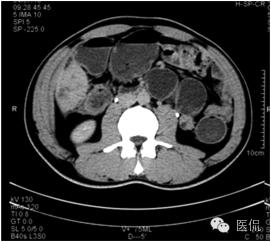

动脉期病灶显示小片状低密度影内,见不规则环状、核心样点状和间隔轻度强化,形态多种。